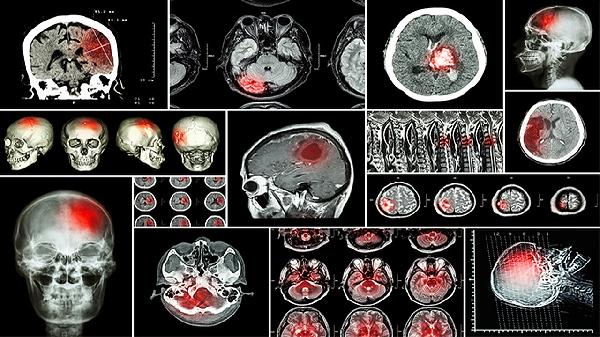

腦腫瘤早期癥狀可能包括頭痛、惡心嘔吐、視力障礙、肢體無力或麻木以及癲癇發(fā)作。這些表現(xiàn)與腫瘤位置、大小及生長速度有關(guān),早期識別有助于及時就醫(yī)。

腦腫瘤引起的頭痛是常見的早期信號,通常表現(xiàn)為持續(xù)性鈍痛,在清晨起床時或咳嗽、用力后加重。這種頭痛與普通緊張性頭痛不同,服用常規(guī)止痛藥效果不佳。頭痛的發(fā)生與腫瘤占位導(dǎo)致顱內(nèi)壓增高或直接壓迫腦膜血管神經(jīng)有關(guān)?;颊呖赡芡瑫r感到頭部有壓迫感。出現(xiàn)此類進行性加重的頭痛,建議及時進行頭顱影像學(xué)檢查以明確診斷。

腫瘤生長可能壓迫視神經(jīng)或視交叉,或?qū)е嘛B內(nèi)壓增高引發(fā)視乳頭水腫,從而影響視力?;颊咴缙诳赡芨械揭曃锬:⒁暳ο陆?、視野缺損,例如看不到某一側(cè)的物體,或者看到閃光、黑影。這些視覺變化有時會被誤認為是眼部疲勞或近視加深。定期眼科檢查若發(fā)現(xiàn)視乳頭水腫,需高度警惕顱內(nèi)病變可能。

腦腫瘤的早期癥狀多樣且缺乏特異性,容易與其他疾病混淆。保持健康的生活方式,如均衡飲食、適度鍛煉、避免頭部外傷和減少電離輻射暴露,可能對降低風(fēng)險有潛在幫助。但更重要的是提高警惕,一旦出現(xiàn)上述進行性加重的神經(jīng)系統(tǒng)癥狀,尤其是多種癥狀合并出現(xiàn)時,應(yīng)毫不猶豫地前往神經(jīng)內(nèi)科或神經(jīng)外科就診,通過頭顱CT或磁共振等檢查明確診斷。早期發(fā)現(xiàn)和治療是改善腦腫瘤預(yù)后的關(guān)鍵。